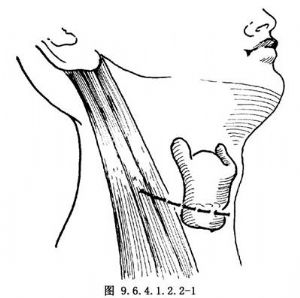

9.2 2.體位及切口

取平臥位,頭偏向對側。頸部皮膚常規消毒,以無菌巾包頭,鋪巾。平甲狀軟骨下緣、自正中線沿皮紋向後達胸鎖乳突肌前緣做切口,切開皮膚、皮下組織及頸闊肌(圖9.6.4.1.2.2-1)。